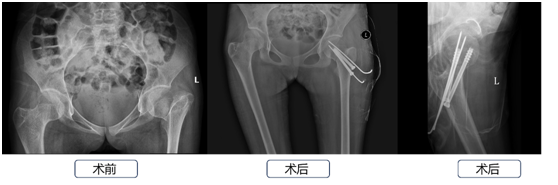

2023年04月19日,郑州院区髋关节外二科迎来了一位特殊的小患者,今年14岁,自幼失去父母,家庭非常贫困,因外伤导致左侧股骨颈骨折。刘立云副主任医师接诊后第一时间便根据患者病史、影像资料、体格检查等信息制定了详细的诊疗方案(股骨颈骨折切开复位空心钉内固定术 支具外固定术)。鉴于患者处于生长发育时期,刘立云副主任医师经过多方努力从省外寻求到与患者骨骼相匹配的7.0mm股骨颈空心钉。